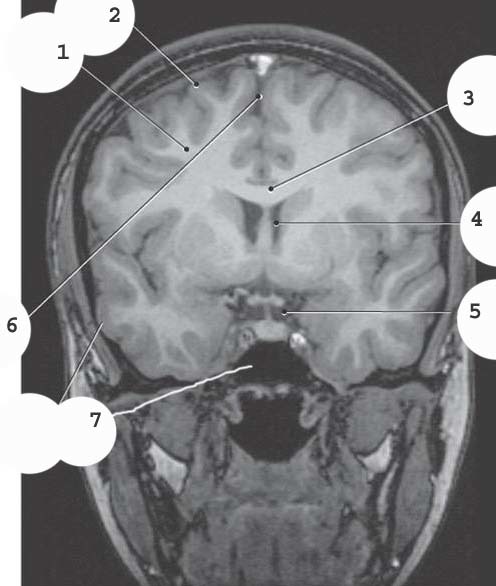

1

Longitudinal Fissure

White matter

2

gray matter

4

lateral ventricle

5

suprasellar cistern

6

7

sphenoid sinus